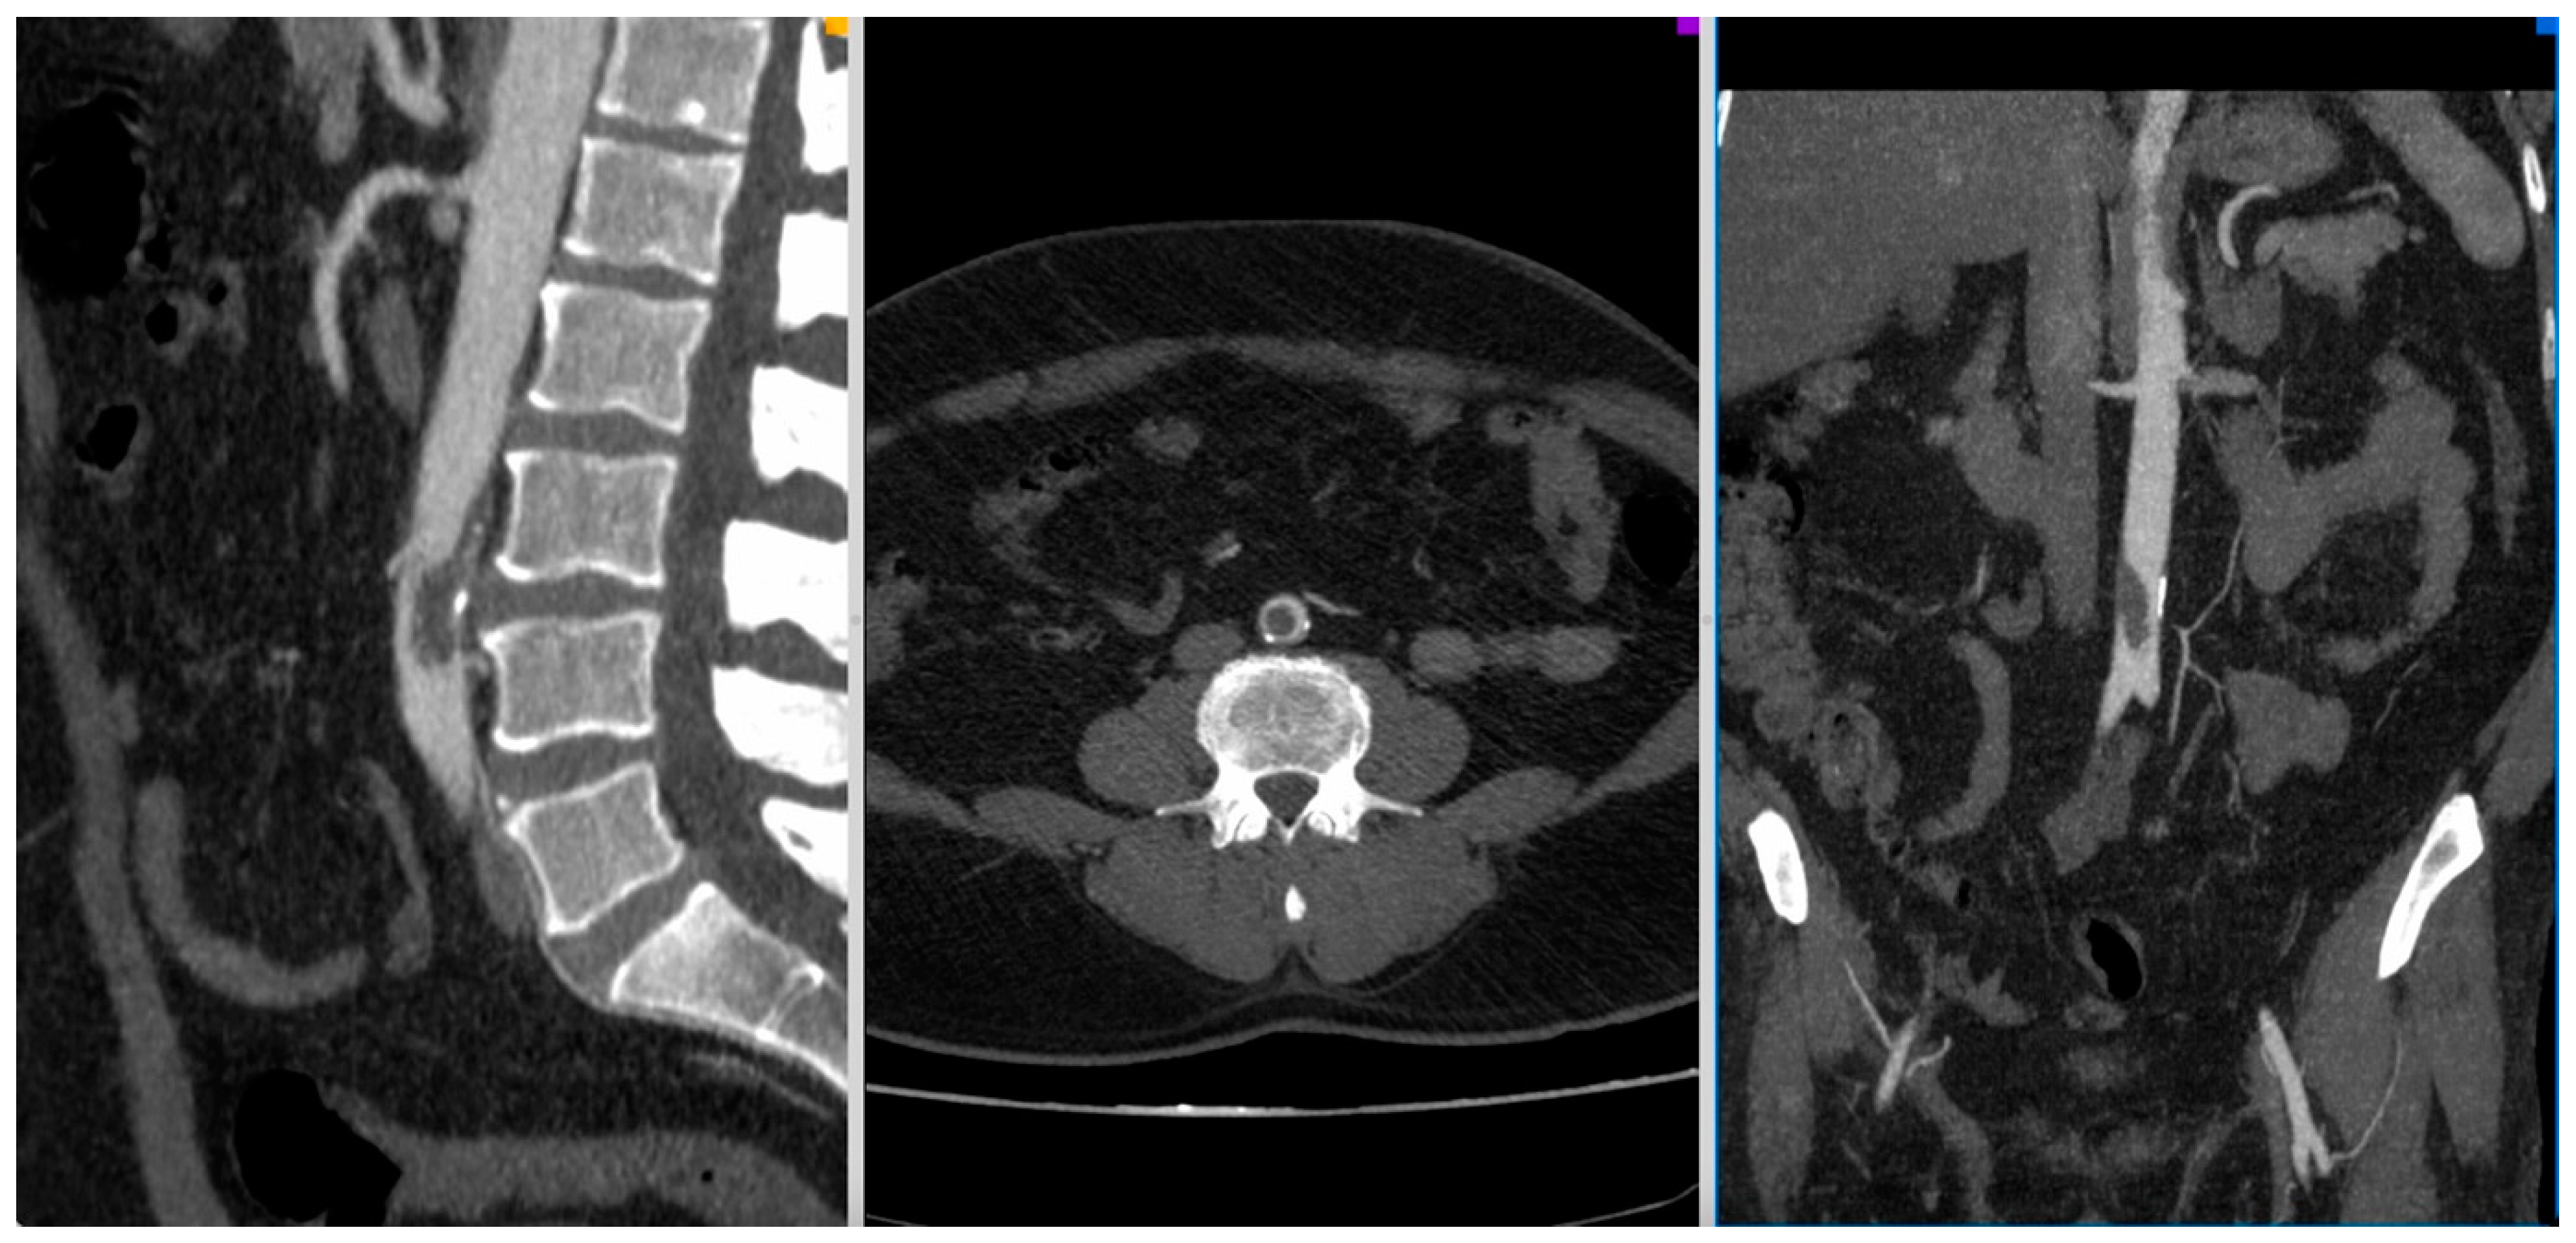

Figure 1.

CT-Angio of a 52 yo patient with aortic thrombosis with acute right lower limb ischemia 8 days after SARS-CoV-2 diagnosis.